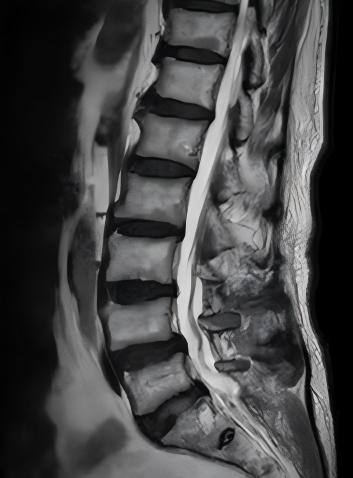

术后

“让台州的老人家不用遭罪,在家门口就能看好病,安安稳稳过日子,就是我们最大的心愿。”李宏杰主任说,接下来团队还会继续打磨技术、优化流程,让更多被脊柱问题困扰的高龄患者,都能重新“挺直腰杆”,安享晚年。